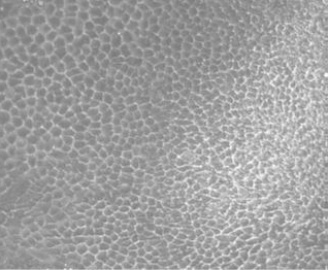

Phase contrast image of RPE cell

Photo Credit: The Eye-Bank for Sight Restoration